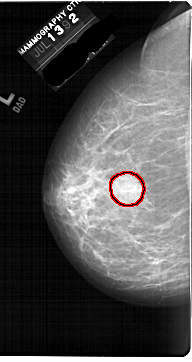

FILE: A_1688_1.LEFT_MLO.OVERLAY

TOTAL_ABNORMALITIES 1

ABNORMALITY 1

LESION_TYPE MASS SHAPE ROUND MARGINS ILL_DEFINED

ASSESSMENT 4

SUBTLETY 4

PATHOLOGY BENIGN

TOTAL_OUTLINES 1

BOUNDARY